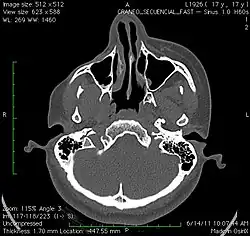

A 3D, soft tissue reconstruction of a CT scan of a 17-year-old girl with Parry Romberg syndrome. -

CT scan 3D bone reconstruction of a 17-year-old girl with Parry Romberg syndrome.